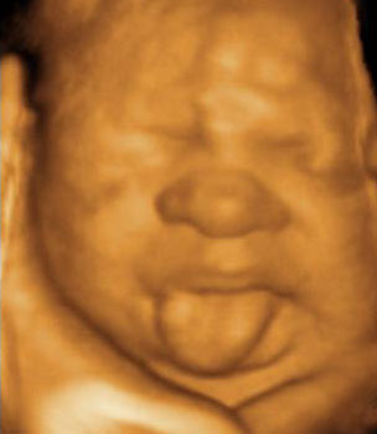

What is Macroglossia?

Protrusion or enlarged tongue

What is macroglossia associated with?

Beckwith-Wiedemann Syndrome

Trisomy 21

What is this image showing?

Macroglossia